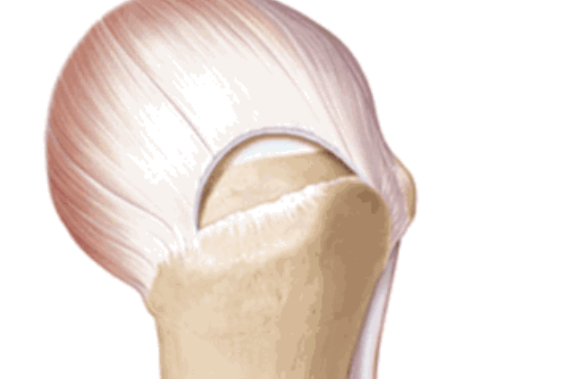

按照损伤程度分为部分撕裂( MR准确性>85% )和完全撕裂(MR准确性>95% )。

按照撕裂的形状又分为新月形撕裂、U形撕裂、L形撕裂、倒L形撕裂、巨大回缩性/不可移动性撕裂。想要判断损伤的形状需要在MRI上利用多个平面、多张照片来分析。